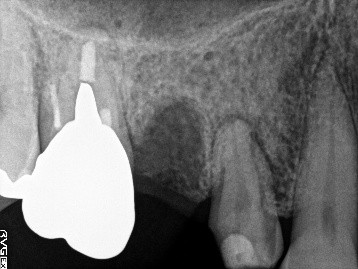

ブリッジの支台になっている奥の歯が、被せ物の中で虫歯になり、支台の役割を果たさず、前方の歯のみで支えられていました。前方の歯をそのままにして、後方の部分を切り離すと、そのまま取れてきました。中は、虫歯で歯根しか残っていない状況でした。この歯は、根管治療後、単独でオールセラミック冠を被せ、歯のないところにインプラントを埋入しました。

冠の中で大きな虫歯になり支台の役割を果たしていませんでした。

【インプラント埋入前】

冠はブリッジを切断しただけで取れてきました。軟化象牙質を取り除いたところ、歯根しか残っていない状況で保存できるかどうかのぎりぎりのところでした。